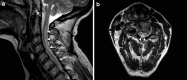

Acquired copper deficiency has been recognised as a rare cause of anaemia and neutropenia for over half a century. Copper deficiency myelopathy (CDM) was only described within the last decade, and represents a treatable cause of non-compressive myelopathy which closely mimics subacute combined degeneration due to vitamin B12 deficiency. Here, 55 case reports from the literature are reviewed regarding their demographics, aetiology, haematological and biochemical parameters, spinal imaging, treatment and outcome. The pathophysiology of disorders of copper metabolism is discussed. CDM most frequently presented in the fifth and sixth decades and was more common in women (F:M = 3. 6:1). Risk factors included previous upper gastrointestinal surgery, zinc overload and malabsorption syndromes, all of which impair copper absorption in the upper gastrointestinal tract. No aetiology was established in 20% of cases. High zinc levels were detected in some cases not considered to have primary zinc overload, and in this situation the contribution of zinc to the copper deficiency state remained unclear. Cytopenias were found in 78%, particularly anaemia, and a myelodysplastic syndrome may have been falsely diagnosed in the past. Spinal MRI was abnormal in 47% and usually showed high T2 signal in the posterior cervical and thoracic cord. In a clinically compatible case, CDM may be suggested by the presence of one or more risk factors and/or cytopenias. Low serum copper and caeruloplasmin levels confirmed the diagnosis and, in contrast to Wilson's disease, urinary copper levels were typically low. Treatment comprised copper supplementation and modification of any risk factors, and led to haematological normalisation and neurological improvement or stabilisation. Since any neurological recovery was partial and case numbers of CDM will continue to rise with the growing use of bariatric gastrointestinal surgery, clinical vigilance will remain the key to minimising neurological sequelae. Recommendations for treatment and prevention are made VSports手机版. .